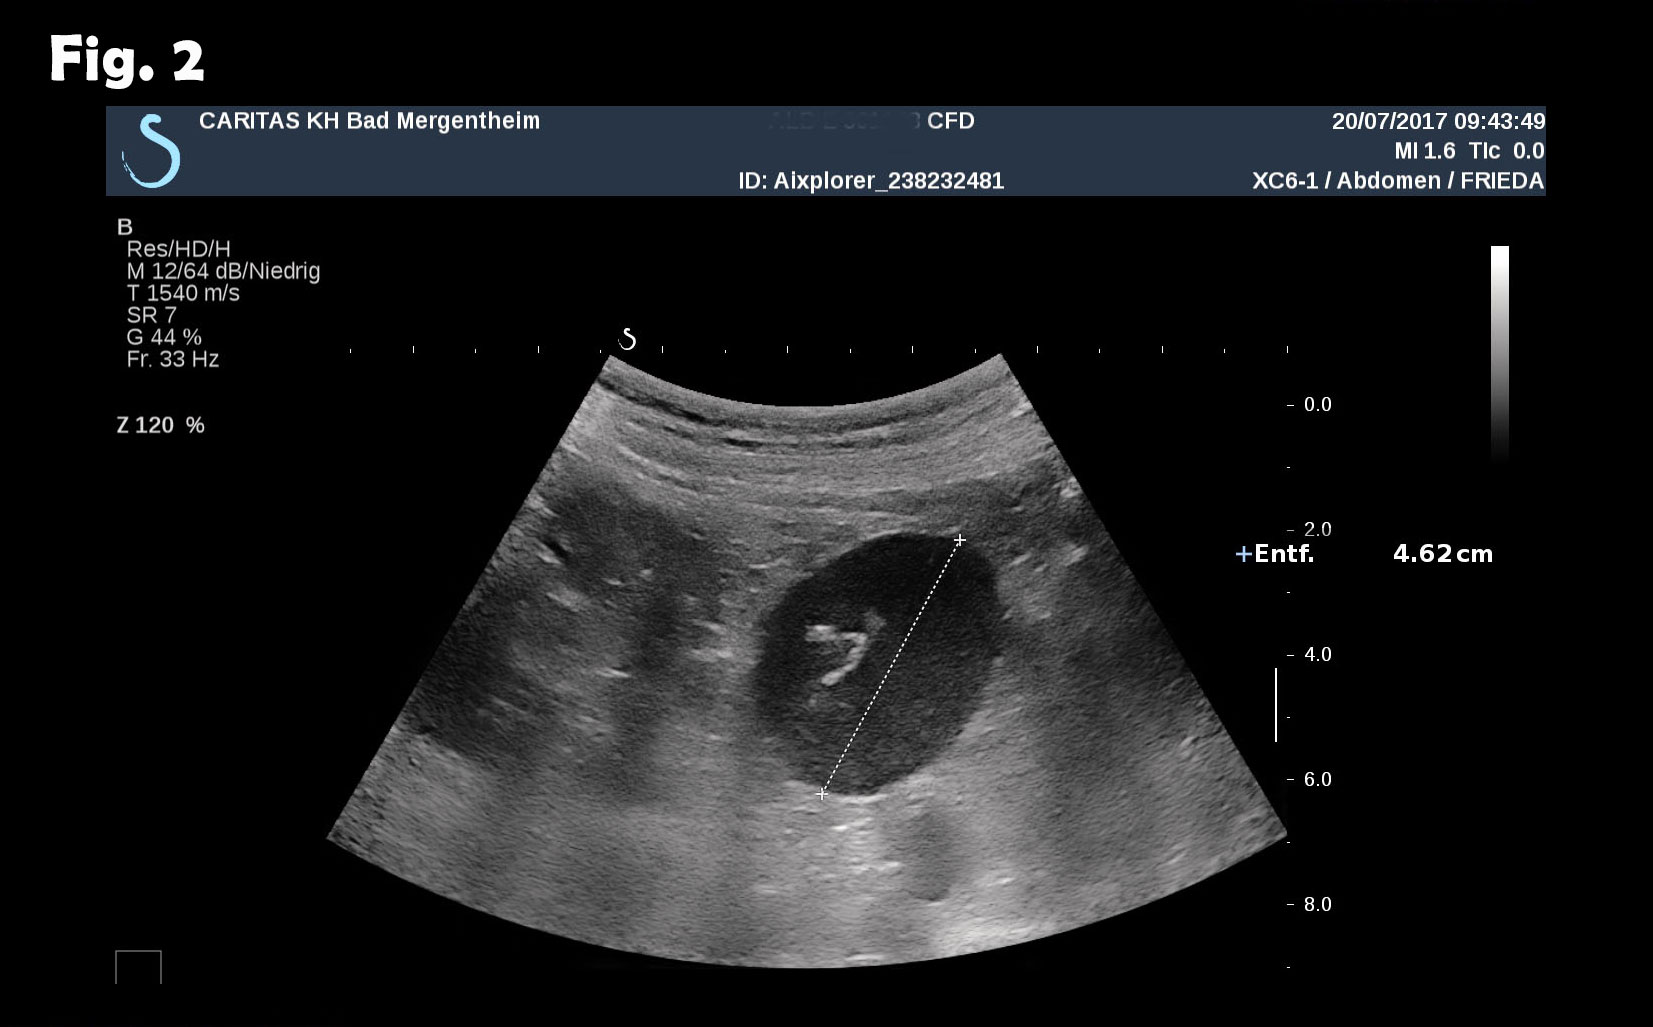

Computed tomography of the chest revealed pneumonic infiltration but was otherwise normal. The endoscopic examination of the upper and lower gastrointestinal tract was normal. Contrast enhanced ultrasound (CEUS) showed arterial and late phase enhancement lasting more than 5 minutes in all examined nodules. After Biopsy the ultrasound examination was performed showing multiple almost echofree but also echogenic round and oval shaped focal peritoneal masses with a size of up to 46 mm [Figure 2-4].

Figure 2: B-mode ultrasound of the abdominal lesion(s). The largest and almost echofree lesion (46 mm) was identified.